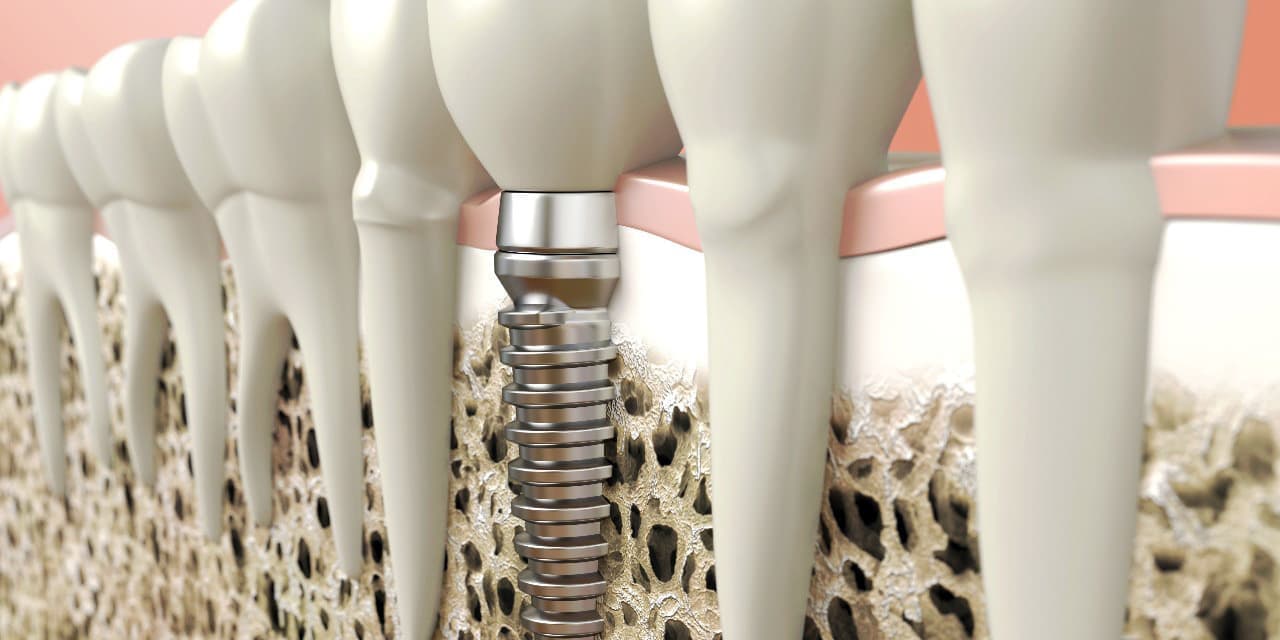

インプラントとは、顎の骨に人工歯根となる金属を埋め込み、それを土台にして、天然の歯と同じような人工の歯を取り付ける治療方法です。

埋め込む金属に生体との親和性が高いチタンが使われる事が多く、チタンは長年の臨床研究でインプラントの素材として最も安全であり、また顎の骨としっかり結合することが確認されています。

インプラントは周りの歯を傷つけず、残った歯への影響が少ないため、自分の歯を多く残せます。

また顎の骨がやせるのを防げる効果もあります。